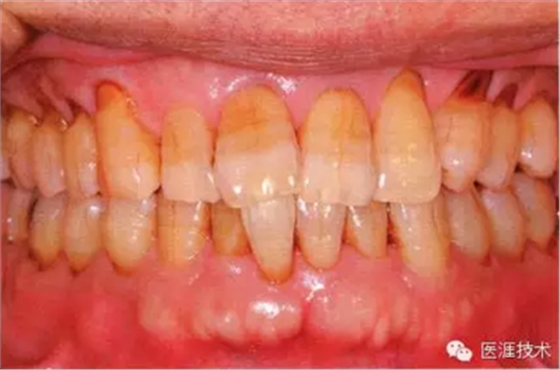

55歲牙周炎男性的臨床照片

55歲男性抽煙患者(1天20支、抽煙35年)。菌斑控制得不好。通過牙周探診,全頜有4~9mm的牙周袋,有1~3度的根分叉部病變。通過X光片觀察,上頜前牙中度牙槽骨吸收,其他地方有中度牙槽骨吸收。受吸煙影響,牙齦纖維性肥厚,呈紅黑色。牙齦幾乎沒有浮腫和發(fā)紅,所以這個病例是從外觀上無法預(yù)測病癥嚴重程度的病例。